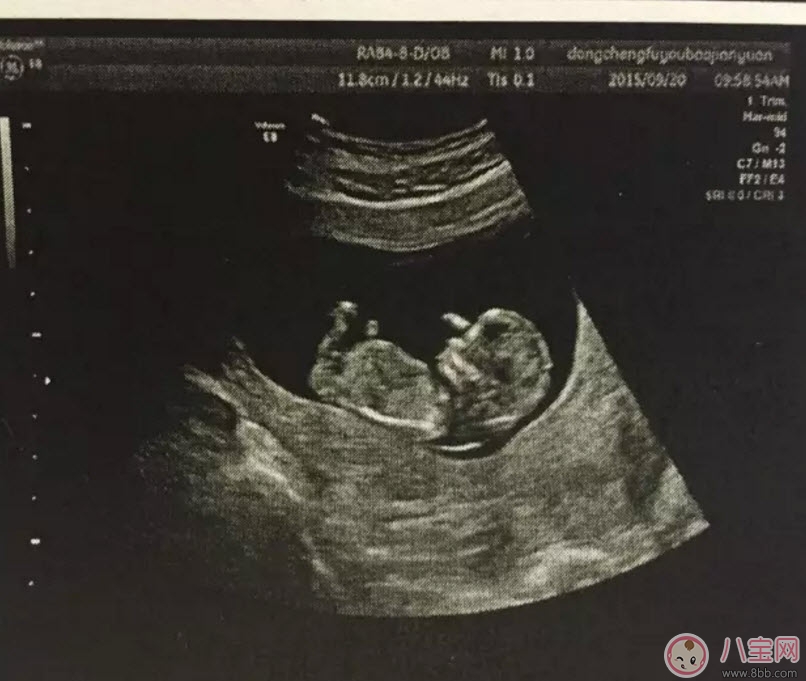

什么情况下使用普通B超孕早期的时候用普通B超就可以了,早期只是检测胎儿大概情况,比如检测是否在宫内、胎儿的头围、股骨长、羊水等指标 。一般在怀孕8-12周做一次黑白B超确定在宫内和胎龄 。二维B超适用于孕早期 。二维B超是最普通的B超,它采用的是黑白超声诊断技术,即通过超声探头测得的是黑白图像,且只能观测到胎儿的组织结构,测量出胎儿头部、身体的长度,内脏、骨骼的大小和形态,以及是否有畸形 。